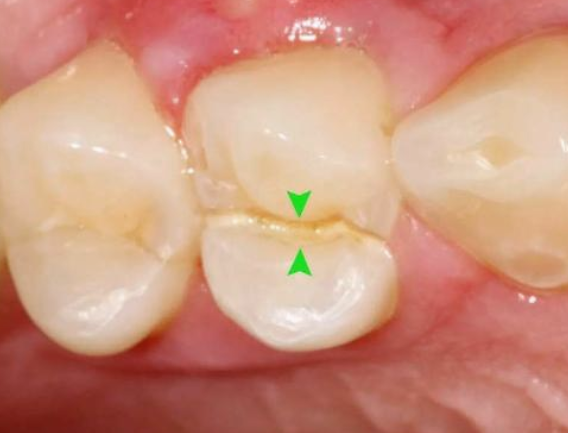

1、牙髓炎:牙髓因細(xì)菌感染而發(fā)炎。在密封的牙髓腔中,牙髓通常不會(huì)被細(xì)菌感染。當(dāng)牙齒因齲齒而開(kāi)孔時(shí),該孔太深,外部細(xì)菌會(huì)侵入牙髓腔,從而感染骨髓。

3、牙髓裸露:當(dāng)牙齒折斷并且牙齒的神經(jīng)暴露時(shí),通常需要進(jìn)行根管治療。